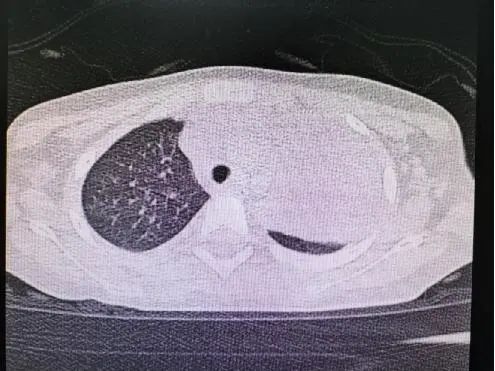

肺炎支原体肺炎的肺部体征及肺部影像学特点呈多样性改变,婴儿期可有湿性啰音,有时可呈梗阻性肺气肿体征。年长儿往往缺乏显著的胸部体征。肺炎支原体肺炎X线表现多样,有时仅为肺门阴影增重,多数呈不整齐云雾状肺浸润影,少数为大叶性实变影,可见肺不张,肺部阴影可呈游走性。CT大多数表现为磨玻璃样改变及肺间质性改变,体征轻微而胸片阴影显著,是本病特征之一。重症支原体肺炎时,可出现大叶性实变、坏死性肺炎、胸腔积液等。从目前住院患儿看,今年肺炎支原体感染所导致的大叶性肺炎明显高于往年。